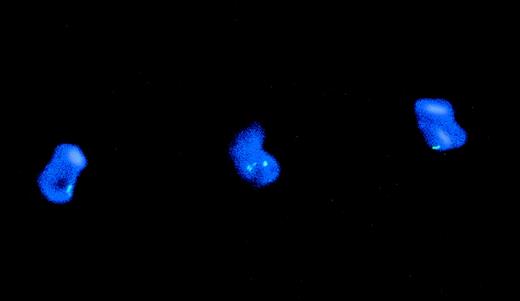

The initial PBMC population contained 95% leukemia cells. The maintenance of expression of CD34 by the cytokine-induced DC provided substantial evidence that the DC were of leukemic origin rather than from a minor population of normal precursors in the PBMC. To further assess whether the DC were of leukemic origin, the induced DC population was analyzed for chromosome 7 monosomy by FISH. To obtain a more homogeneous DC population for analysis, CD80+ cultured cells were positively selected by immunomagnetic sorting. Before sorting, 35% of cultured cells expressed CD80. All of the original blasts and 94% of sorted CD80+ cells showed chromosome 7 monosomy (Fig 2). Interphase nuclei from normal PBMC, which were used as a control, showed a false-positive background of 5%.

Genotype of CD80-sorted, leukemia-derived DC (patient TA). The figure shows DAPI counterstained nuclei from a CD80-sorted positive culture of leukemia-derived DC hybridized with a chromosome 7-satellite (green signal) probe. Cells with 1 signal indicating monosomy 7 or 2 signals indicating the normal pattern are shown.

To examine the leukemic origin of the DC, cells from day 7 of culture were positively selected according to CD83 expression and examined for the presence of the bcr-abl fusion gene by FISH. Before culture, 74% of unfractionated blasts were bcr-abl positive. After culture, 27% of CD83-sorted positive cells were bcr-abl+(Fig 6). Cells from a normal control PBMC culture showed 4 of 100 interphase nuclei analyzed with a fusion signal, giving a background false-positive frequency of 4%. Provided that the bcr-abl− blasts observed may not be leukemic cells, the results show that ALL can be induced to differentiate into cells with a DC phenotype, but imply that normal DC precursors may coexist with the leukemic blasts.

Genotype of CD83-sorted, Ph+leukemia-derived DC (patient AB). The figure shows interphase nuclei from a CD83-sorted positive culture of leukemia-derived DC. A normal interphase nucleus shows 2 orange (bcr) and 2 green (abl) signals. Nuclei with bcr-abl fusion show 1 orange signal (bcr), 1 green signal (abl), and the fusion (bcr-abl) orange and green signal (arrow).